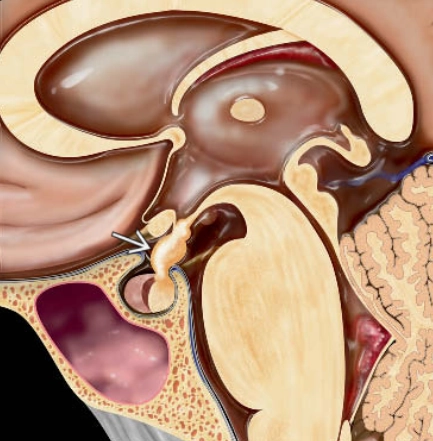

• Tuyến yên sau lạc chỗ (Ectopic posterior pituitary)

• Tồn tại hai tuyến yên (DPG - Duplication of the Pituitary Gland)

• U mô thừa vùng dưới đồi (Hypothalamic hamartomas)

• U nang khe Rathke (Rathke cleft cysts)